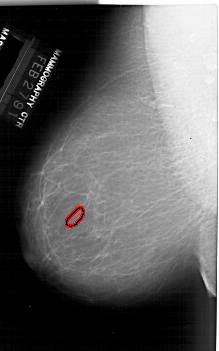

A_1916_1.RIGHT_CC

RIGHT_CC LINES 6451 PIXELS_PER_LINE 3736 BITS_PER_PIXEL 12 RESOLUTION 43.5 NON_OVERLAY

FILE: A_1916_1.LEFT_MLO.OVERLAY

TOTAL_ABNORMALITIES 1

ABNORMALITY 1

LESION_TYPE CALCIFICATION TYPE PUNCTATE DISTRIBUTION CLUSTERED

ASSESSMENT 4

SUBTLETY 1

PATHOLOGY BENIGN

TOTAL_OUTLINES 1